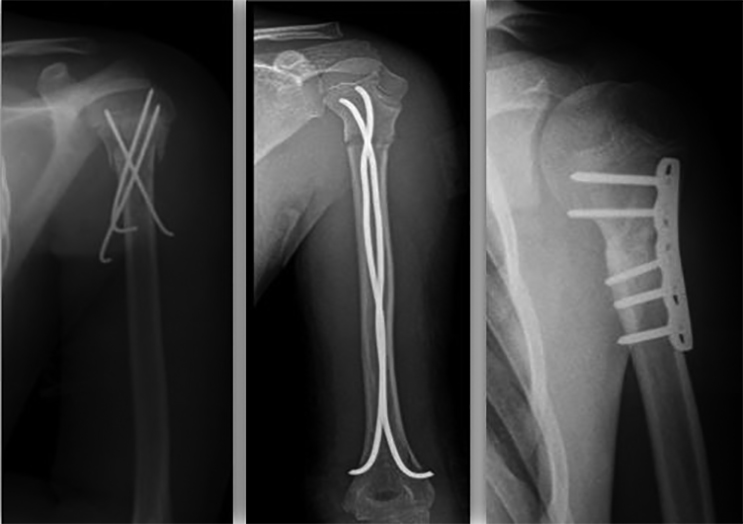

Le principali opzioni di trattamento chirurgico sono: fili di K, ESIN (Elastic Stable Intramedullary Nailing), placca e viti e fissatore esterno (Fig. 1).

I fili di K sono tra i mezzi di sintesi più utilizzati per questo tipo di frattura. I maggiori vantaggi sono legati alla mininvasività, possono infatti essere utilizzati con tecnica percutanea, e al ridotto rischio di complicanze, limitato principalmente all’infezione superficiale dei tramiti (con una frequenza compresa tra il 5 e il 22%), che può essere facilmente risolta con una terapia antibiotica. Per ridurre al massimo il rischio di lesioni iatrogene, il posizionamento dei fili di K deve tenere conto della branca del nervo ascellare (lateralmente) e del nervo muscolocutaneo anteriormente. Il filo di K va posizionato distalmente al nervo ascellare (che decorre a circa 5 cm dall’acromion negli adulti e proporzionalmente meno nei bambini) 8,9.

Solitamente 2, 3 o in alcuni casi 4 fili di K vengono posizionati per stabilizzare la frattura. Il diametro utilizzato è solitamente compreso tra i 2 e i 2,5 mm, in relazione all’età e alla grandezza del paziente. Idealmente, i fili non devono incrociarsi a livello della frattura. Un ulteriore vantaggio dell’utilizzo di questi mezzi di sintesi è legato alla facile e veloce rimozione anche in ambiente ambulatoriale 9.

Gli ESIN, in utilizzo dalla metà degli anni 80, sono dei chiodi elastici da applicare all’interno del canale endomidollare, e trovano indicazione solamente in ortopedia pediatrica. Tra i vantaggi principali si riscontrano la mininvasività, l’ottima possibilità di controllare il dolore, la capacità di mantenere la riduzione con scarso rischio di scomposizione secondaria e soprattutto la possibilità di mobilizzazione precoce. Gli outcome funzionali riportati in letteratura sono eccellenti. Rispetto ai fili di K, gli unici svantaggi degli ESIN sono legati a una curva di apprendimento maggiore e a una più difficile rimozione degli stessi. Entrambe le procedure riportano bassi tassi di complicanze e buoni outcome funzionali. L’utilizzo degli ESIN permette però una migliore riduzione anatomica e un più solido mantenimento della riduzione ottenuta 10.

L’osteosintesi con placca e viti viene utilizzata per scomposizioni importanti (Neer-Horowitz 4), in caso di fallimento di trattamento mininvasivo o quando è necessaria una riduzione a cielo aperto. Per tale motivo, questa tecnica è più invasiva e sono riportati tassi di complicanze più alti. L’approccio può essere transdeltoideo o deltoideo-pettorale.